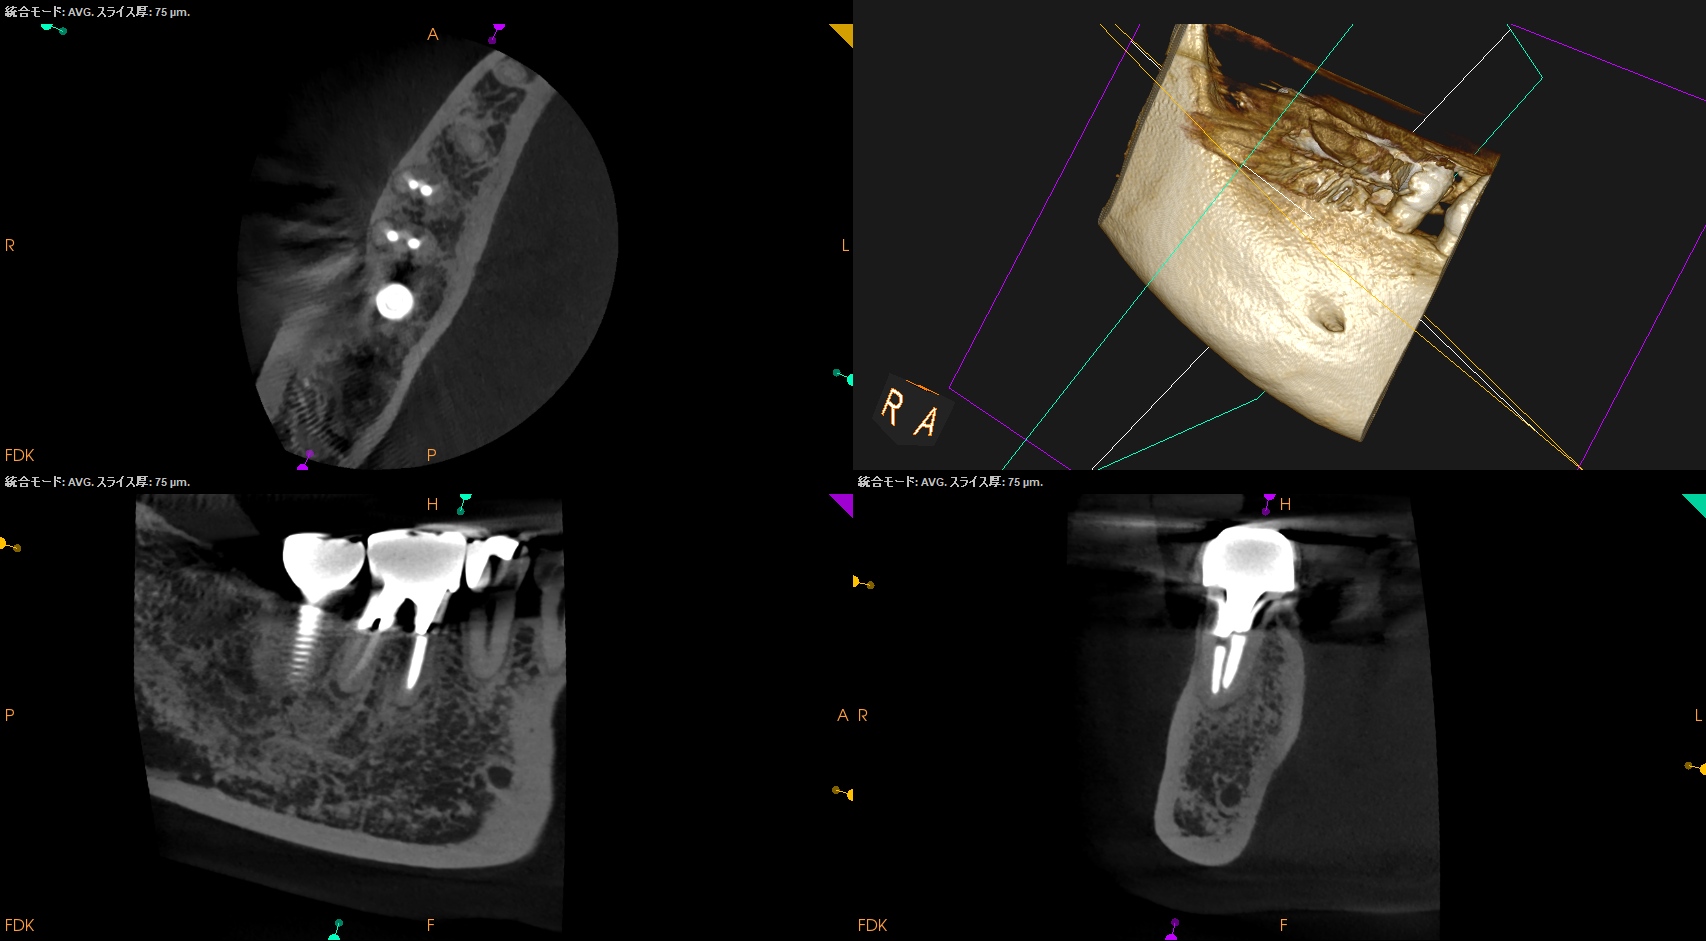

次がDだ。

クラウンのマージン部よりも13mm下方にDのApexがある。

そこに行き着くには歯槽骨を3mm削合する必要がある。

が、ここでミスが起きる。

なぜか?

DのApexを正確に触知していないからだ。

Dの切断部分(Apex)を探索した。

するとそれは無事除去できた。

が、だ。

やはりこのことからも

ApicoectomyではApexの位置を正確に把握する必要がある

ことがわかる。

この医療行為が、今日最も学習になったところだ。

USC時代の教えはやはり生きていた。

Dを逆根管形成し、逆根管充填した。

術後にPA, CBCTを撮影した。

気泡はあるが問題はないとして縫合した。